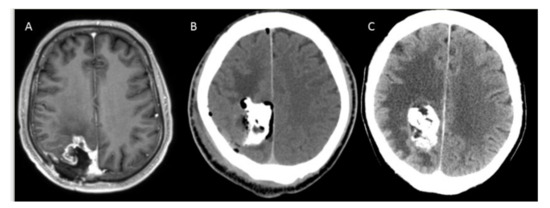

3.2. Safety and Complications